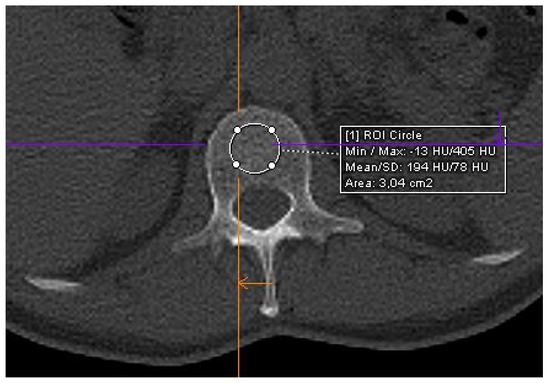

mySurgery | Acute Abdomen。CT of acute abdomen in the elderly | Insights into Imaging。The added value of multidetector CT in the diagnosis of。急性腹症に関するCTの詳細な解説が収められた専門書。- タイトル: CT of Acute Abdomen 第3版- 著者: 荒木 力- 言語: 日本語- 出版社: メディカル・サイエンス・インタ裁断済みのため状態が悪いとしています。ほかの商品とのセットで購入していただける場合値下げ対応いたします。。CT of the Acute Abdomen: GI Applications - Part 1 - YouTube。腰痛 成田崇矢の臨床。【裁断済】心臓血管外科手術 周術期管理のすべて 第2版